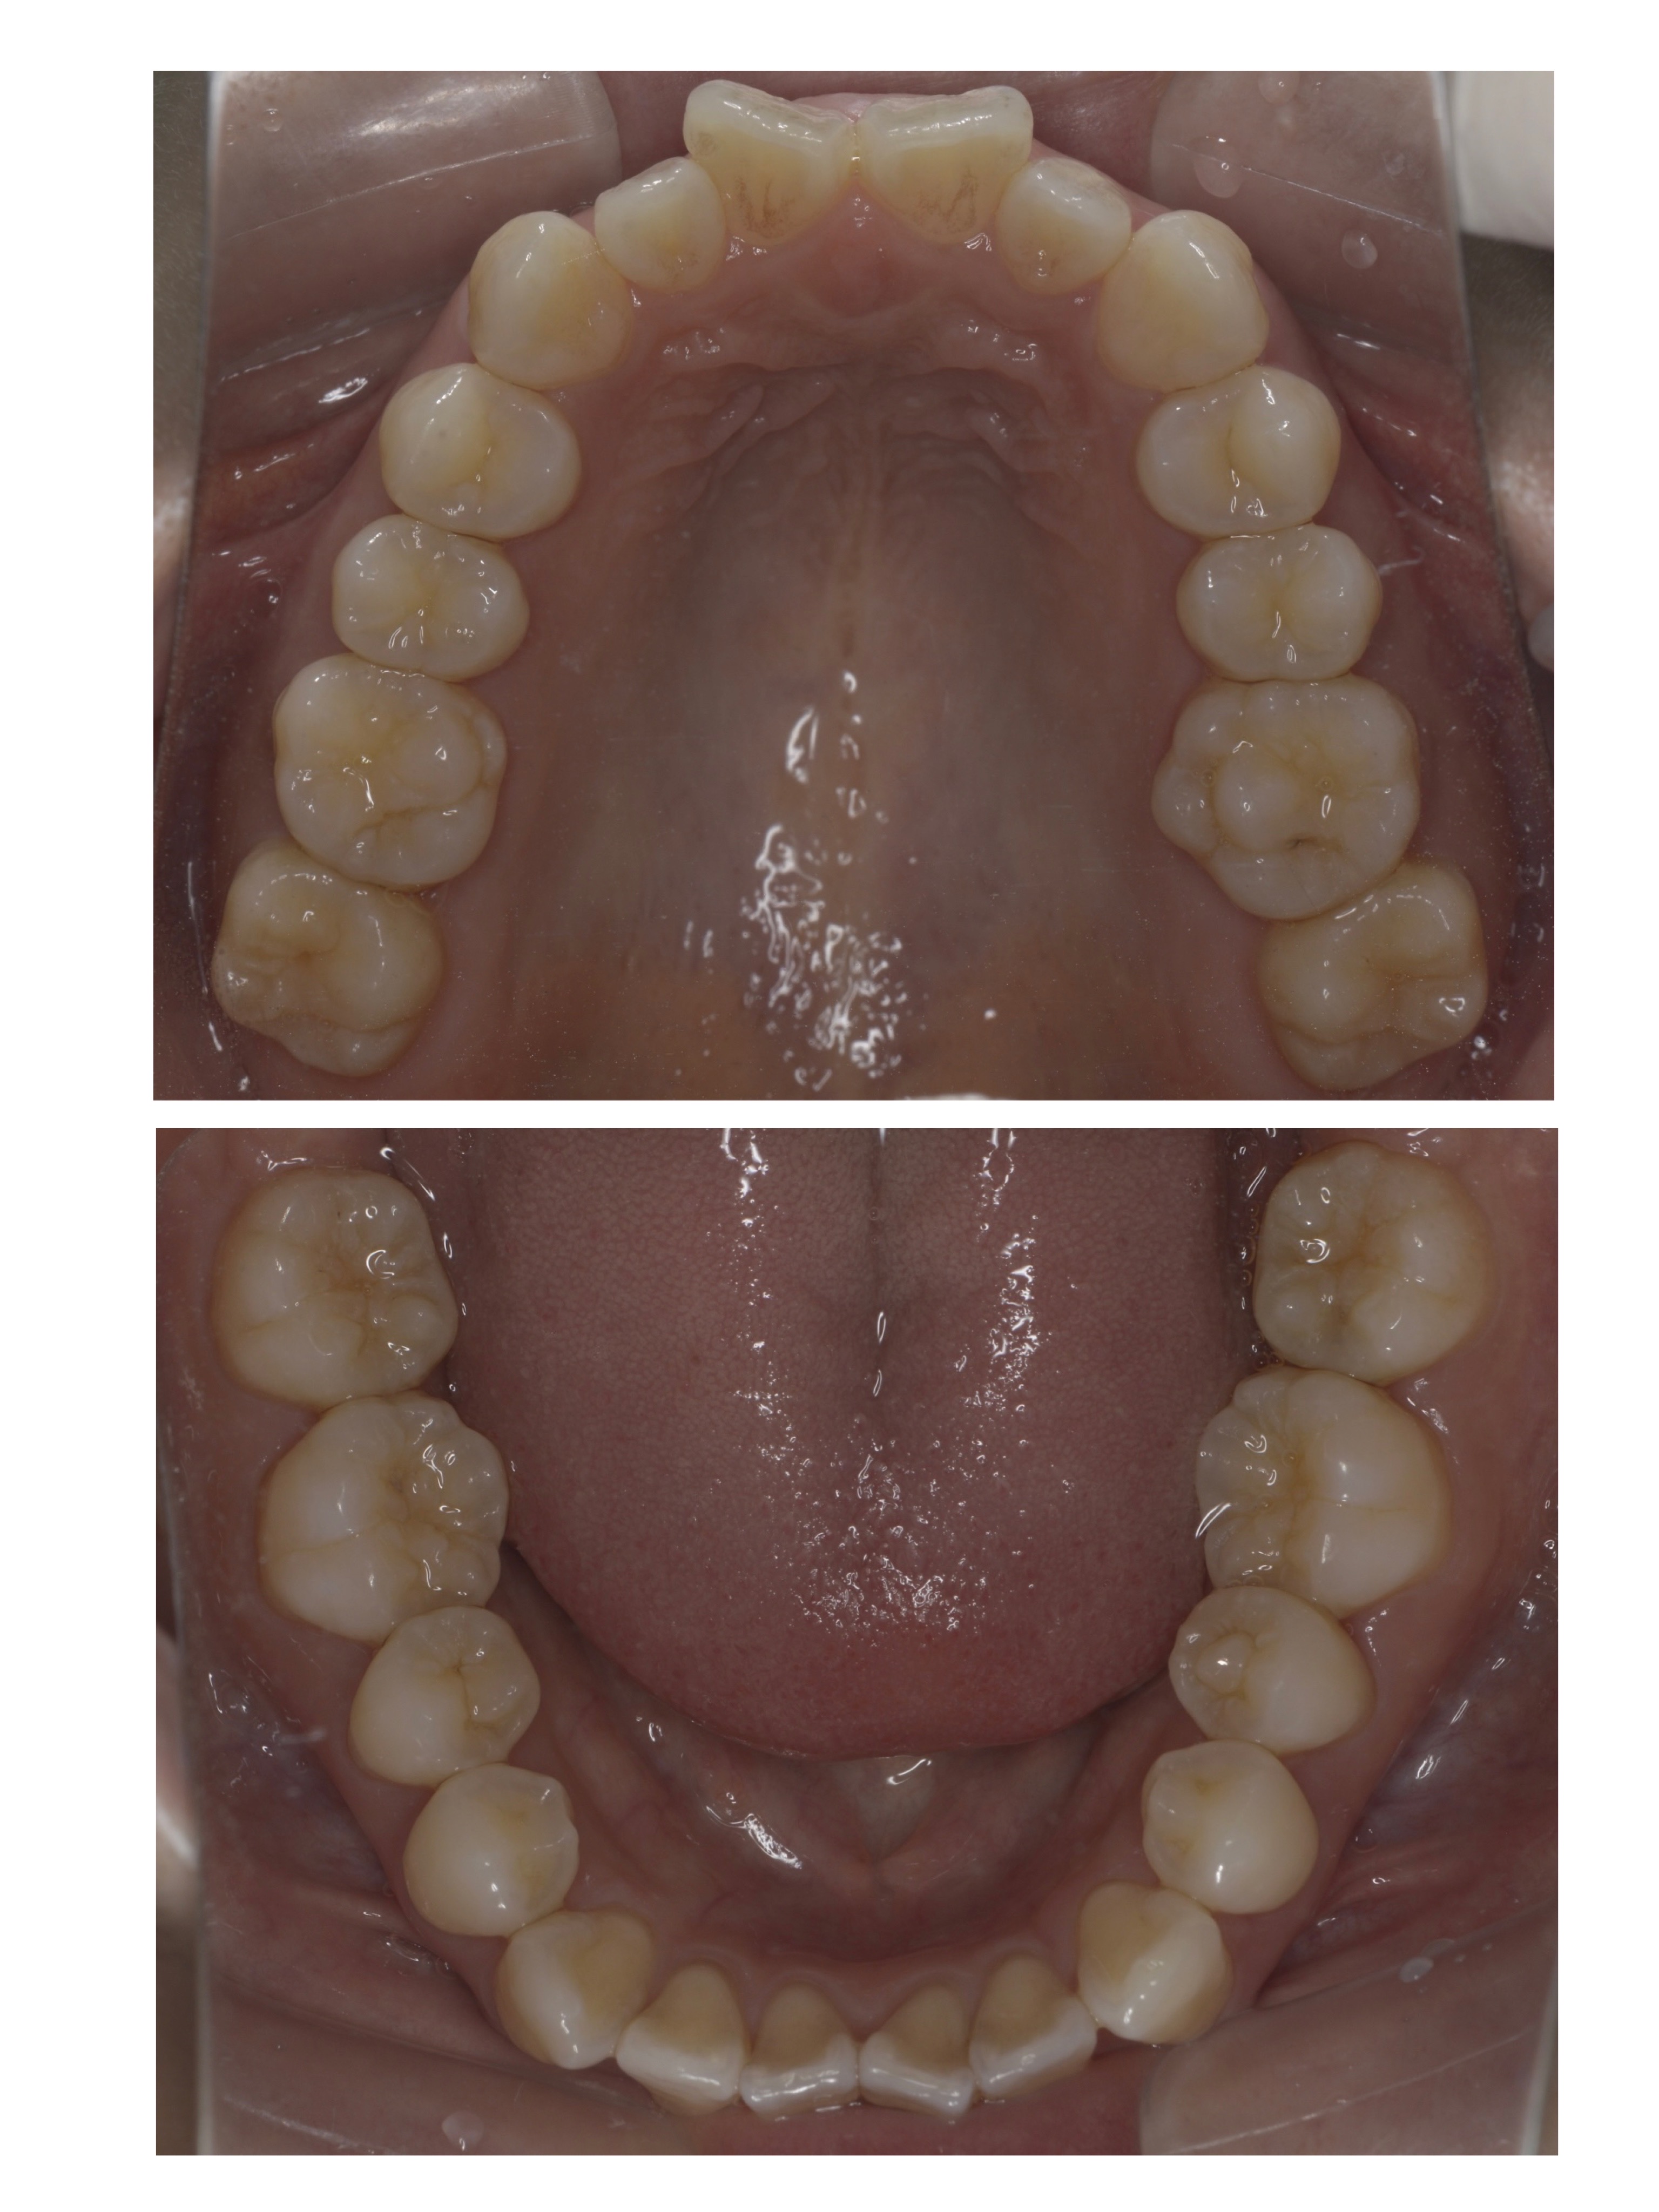

先日、当院に矯正治療に通われている患者様の

治療が終了しました!

約1年半頑張っていただきました!

2021/10/8~2023/3/17

30代女性